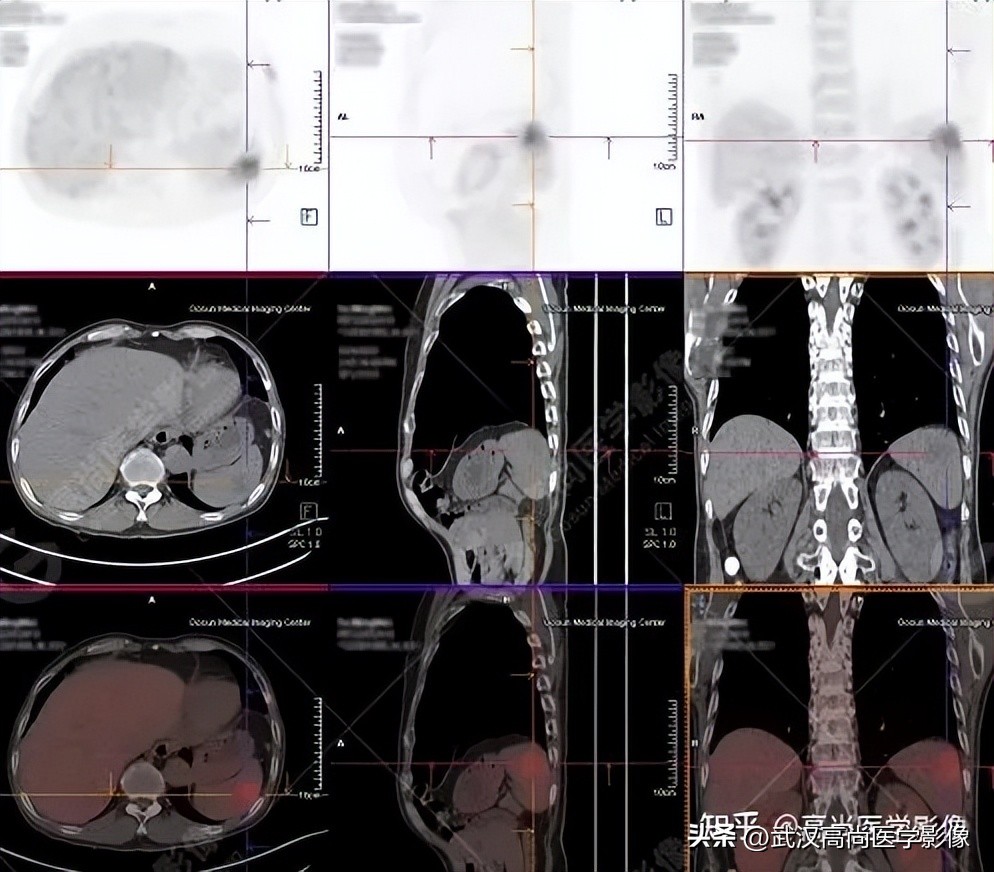

病例三

老年男性63岁,左大腿疼痛1月余,渐加重。

MR检查提示左股骨上段破坏,需排查转移。

左股骨上段溶骨性骨质破坏,SUVmax4.7,怀疑为转移。

全身PET/CT

影像表现:

右肺上叶尖段胸膜下见一实性结节,范围约1.6cm×1.3cm,病灶紧贴邻近胸膜,伴牵拉增厚,FDG高摄取,SUVmax为7.5。

恶性CT征象:

结节边缘不光整,分叶、长短不一的毛刺,邻近胸膜牵拉明显。

右侧胸膜区多发条片状代谢增高影,SUVmax4.7,CT于相应部位胸膜增厚,伴右侧中量胸水。

PET代谢增高,在发现胸膜转移较常规CT扫描有一定的优势。

PET/CT诊断结论

右肺上叶尖段周围型肺癌,累及邻近胸膜;右侧胸膜多发转移,伴中等量胸水;左股骨上段转移。

另外,左肺上叶前段见一团状混杂磨玻璃影,范围约4.3cm×3.3cm,CT值约-662Hu,内部扭曲扩张支气管及血管影穿行,边缘分叶、棘状突起,FDG摄取轻度增高,SUVmax1.3,考虑为多中心起源浸润性肺癌(多原发的肺癌)。